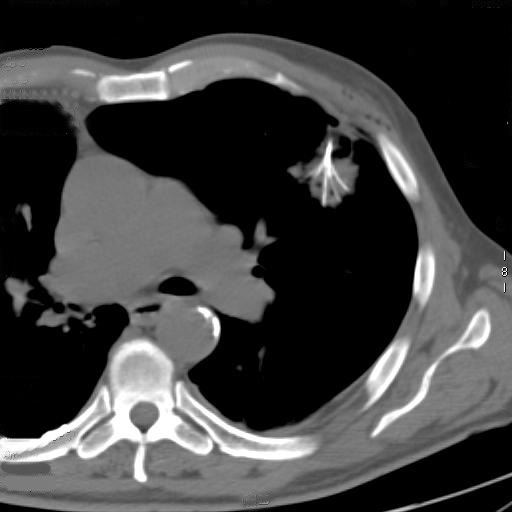

The procedure is performed with the patients under conscious sedation (Ketorolac 0.5-0.8 mg/kg, propofol 1-2 mg/kg/h, and remifentanil 0.1mg/kg/min) and local anesthesia (subcutaneous 1% xylocaine). Vital signs are continuously non-invasively monitored. CT guidance is employed in most of the cases; it is usually enhanced by the administration of contrast material before and after coagulation to obtain information about the real effectiveness of the procedure (Figure 3). In a selected group of patients with the tumour in contact with the thoracic wall, it is possible to work under ultrasound guidance (Video 2). The needle-electrode is inserted through an intercostal space after administration of local anaesthesia (Video 3). The correct placement is confirmed by CT (Figure 4) or ultrasound (Video 4) before applying the radiofrequency energy. The target temperature of ablation is 90°C. It is maintained for a time ranging from 15 to 27 minutes according to the size of the tumor; this variable also determines the gradual deployment of the electrodes, starting from 2 cm and then 1 cm for each step. When technically feasible, the ablation zone should include the whole lesion and one cm of the surrounding lung parenchyma.

Figure 3. By CT guidance it is possible to establish the site, depth, and angle for insertion of the needle electrode.